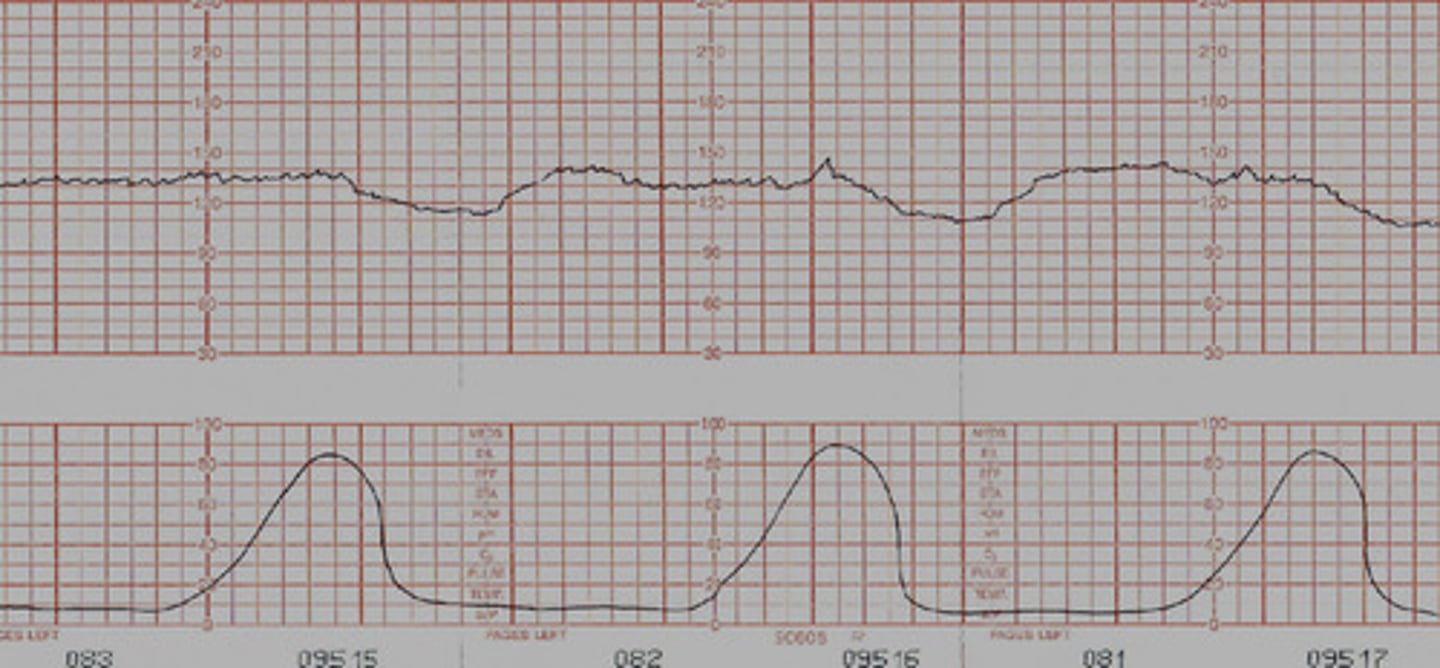

Variable decelerations

- occur at any point with or without a contraction

- r/t cord compression

Nursing interventions for variable decelerations

- change position

- apply oxygen (consistent variables)

Variable (cord compression)